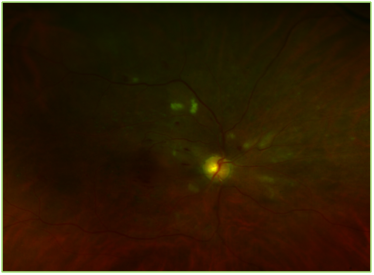

Due to concurrent chemotherapy treatments, the patient was not able to make it to his follow up. He finally presented 6 months later in April 2013, when his vision had reduced to 20/80 OD and OS. At this time, his left APD optic nerve was pale, macular edema was noted in OD and the retinopathy was still present OU. Fluorescein angiogram ordered at that time also showed marked capillary non-perfusion in both eyes, predominantly in the posterior pole region OD. Pan retinal photocoagulation was recommended at this time, however, it was contraindicated due to poor patient cooperation and limited cognitive abilities (Figure 1&2).

Figure 1 Optos image of the right eye showing multiple cotton wool spots, flame shaped and intraretinal hemorrhages and focal laser scars.